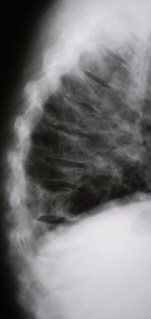

С целью выявления сонографических признаков, характерных для "миеломной почки", УЗИ почек проведено у 60 больных множественной миеломой, у 20 из которых заболевание диагностировано впервые. У 24 (40%) больных, главным образом миеломой Бенс-Джонса, обнаружено увеличение размеров почек. Толщина коркового слоя достигала 2-2,4 см. Выявлялась деформация (иногда раздвоение) чашечного комплекса и контура почек (рис. 9, 10). Расширялась чашечнолоханочная система. Лишь у 4 (7%) больных, страдающих множественной миеломой (у 3 больных миелома Бенс-Джонса и у 1 - G-миелома) в течение 5-7 лет, отмечено уменьшение размеров почек. Толщина их коркового слоя колебалась от 6 до 9 мм, наблюдалась деформация чашечного комплекса, расширение чашечек (>1,5 см) и лоханки (>4 см). При длительном течении болезни уплотнялся корковый слой из-за разрастания интерстициальной ткани (рис. 11). Оценивая результаты гематологического и урологического обследований, следует отметить, что у большинства больных множественной миеломой обнаруживалась гиперпротеинемия и протеинурия различной степени выраженности. По результатам пробы Реберга скорость клубочковой фильтрации (СКФ) у 15 (25%) больных была сниженной до 80-40 мл/мин (норма 80-120 мл/мин), а у 20% - 40-25 мл/мин, при этом минутный диурез составлял 0,5-1 мл/мин (норма 1-1,5 мл/мин). Креатининемия выявлена у 15% больных, а у 33% - установлено высокое содержание мочевины. Анализ реабсорбционной способности почек показал ее нарушение у 33% больных. У 40 (66,6%) пациентов (в пробе Зимницкого) заметно снижалась концентрационная функция почек.

УЗИ почек с множественной миеломой.

Рис. 9. Эхограмма почек больной с впервые диагностированной множественной миеломой.

1 - правая почка;

2 - печень;

3 - левая почка.

УЗИ. Эхограмма почек больной с впервые диагностированной множественной миеломой.

Рис. 10. Эхограмма почек больной с впервые диагностированной множественной миеломой.

УЗИ. Эхограмма почек больной, страдающей множественной миеломой 5 лет.

Рис. 11. Эхограмма почек больной, страдающей множественной миеломой 5 лет.

1 - почки левая и правая.